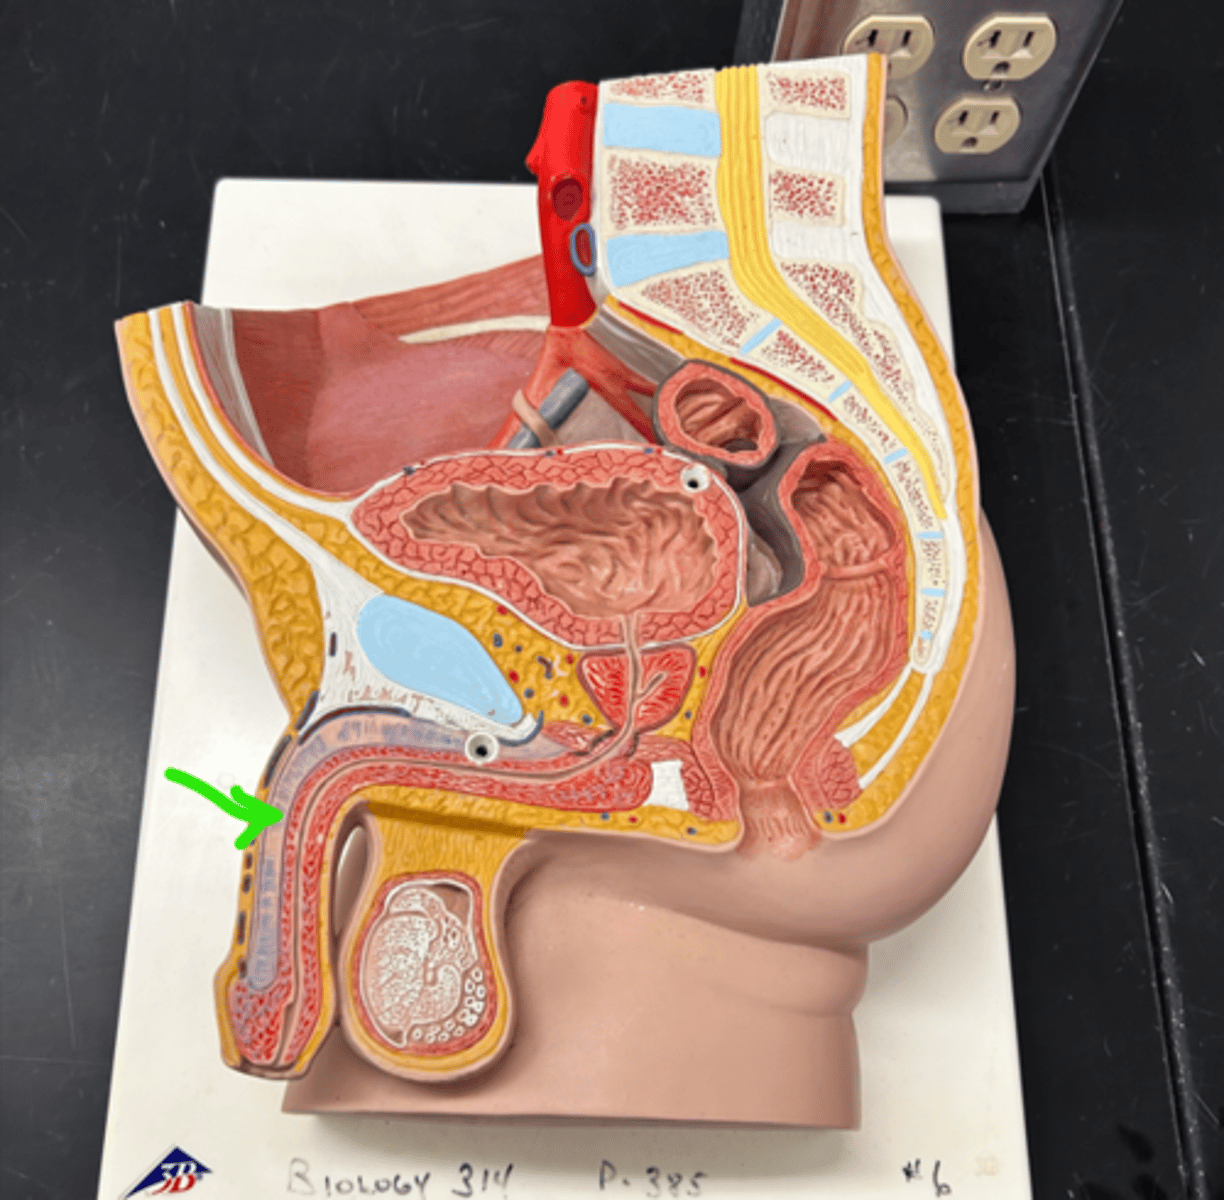

Spermatic cord

Ductus deferens

Ampulla (ductus deferens)

Ejaculatory duct

Seminal gland

Prostate gland

Bulbourethral gland

Urethra

Urethra

Prostatic urethra

Membranous urethra

Spongy urethra

Penis